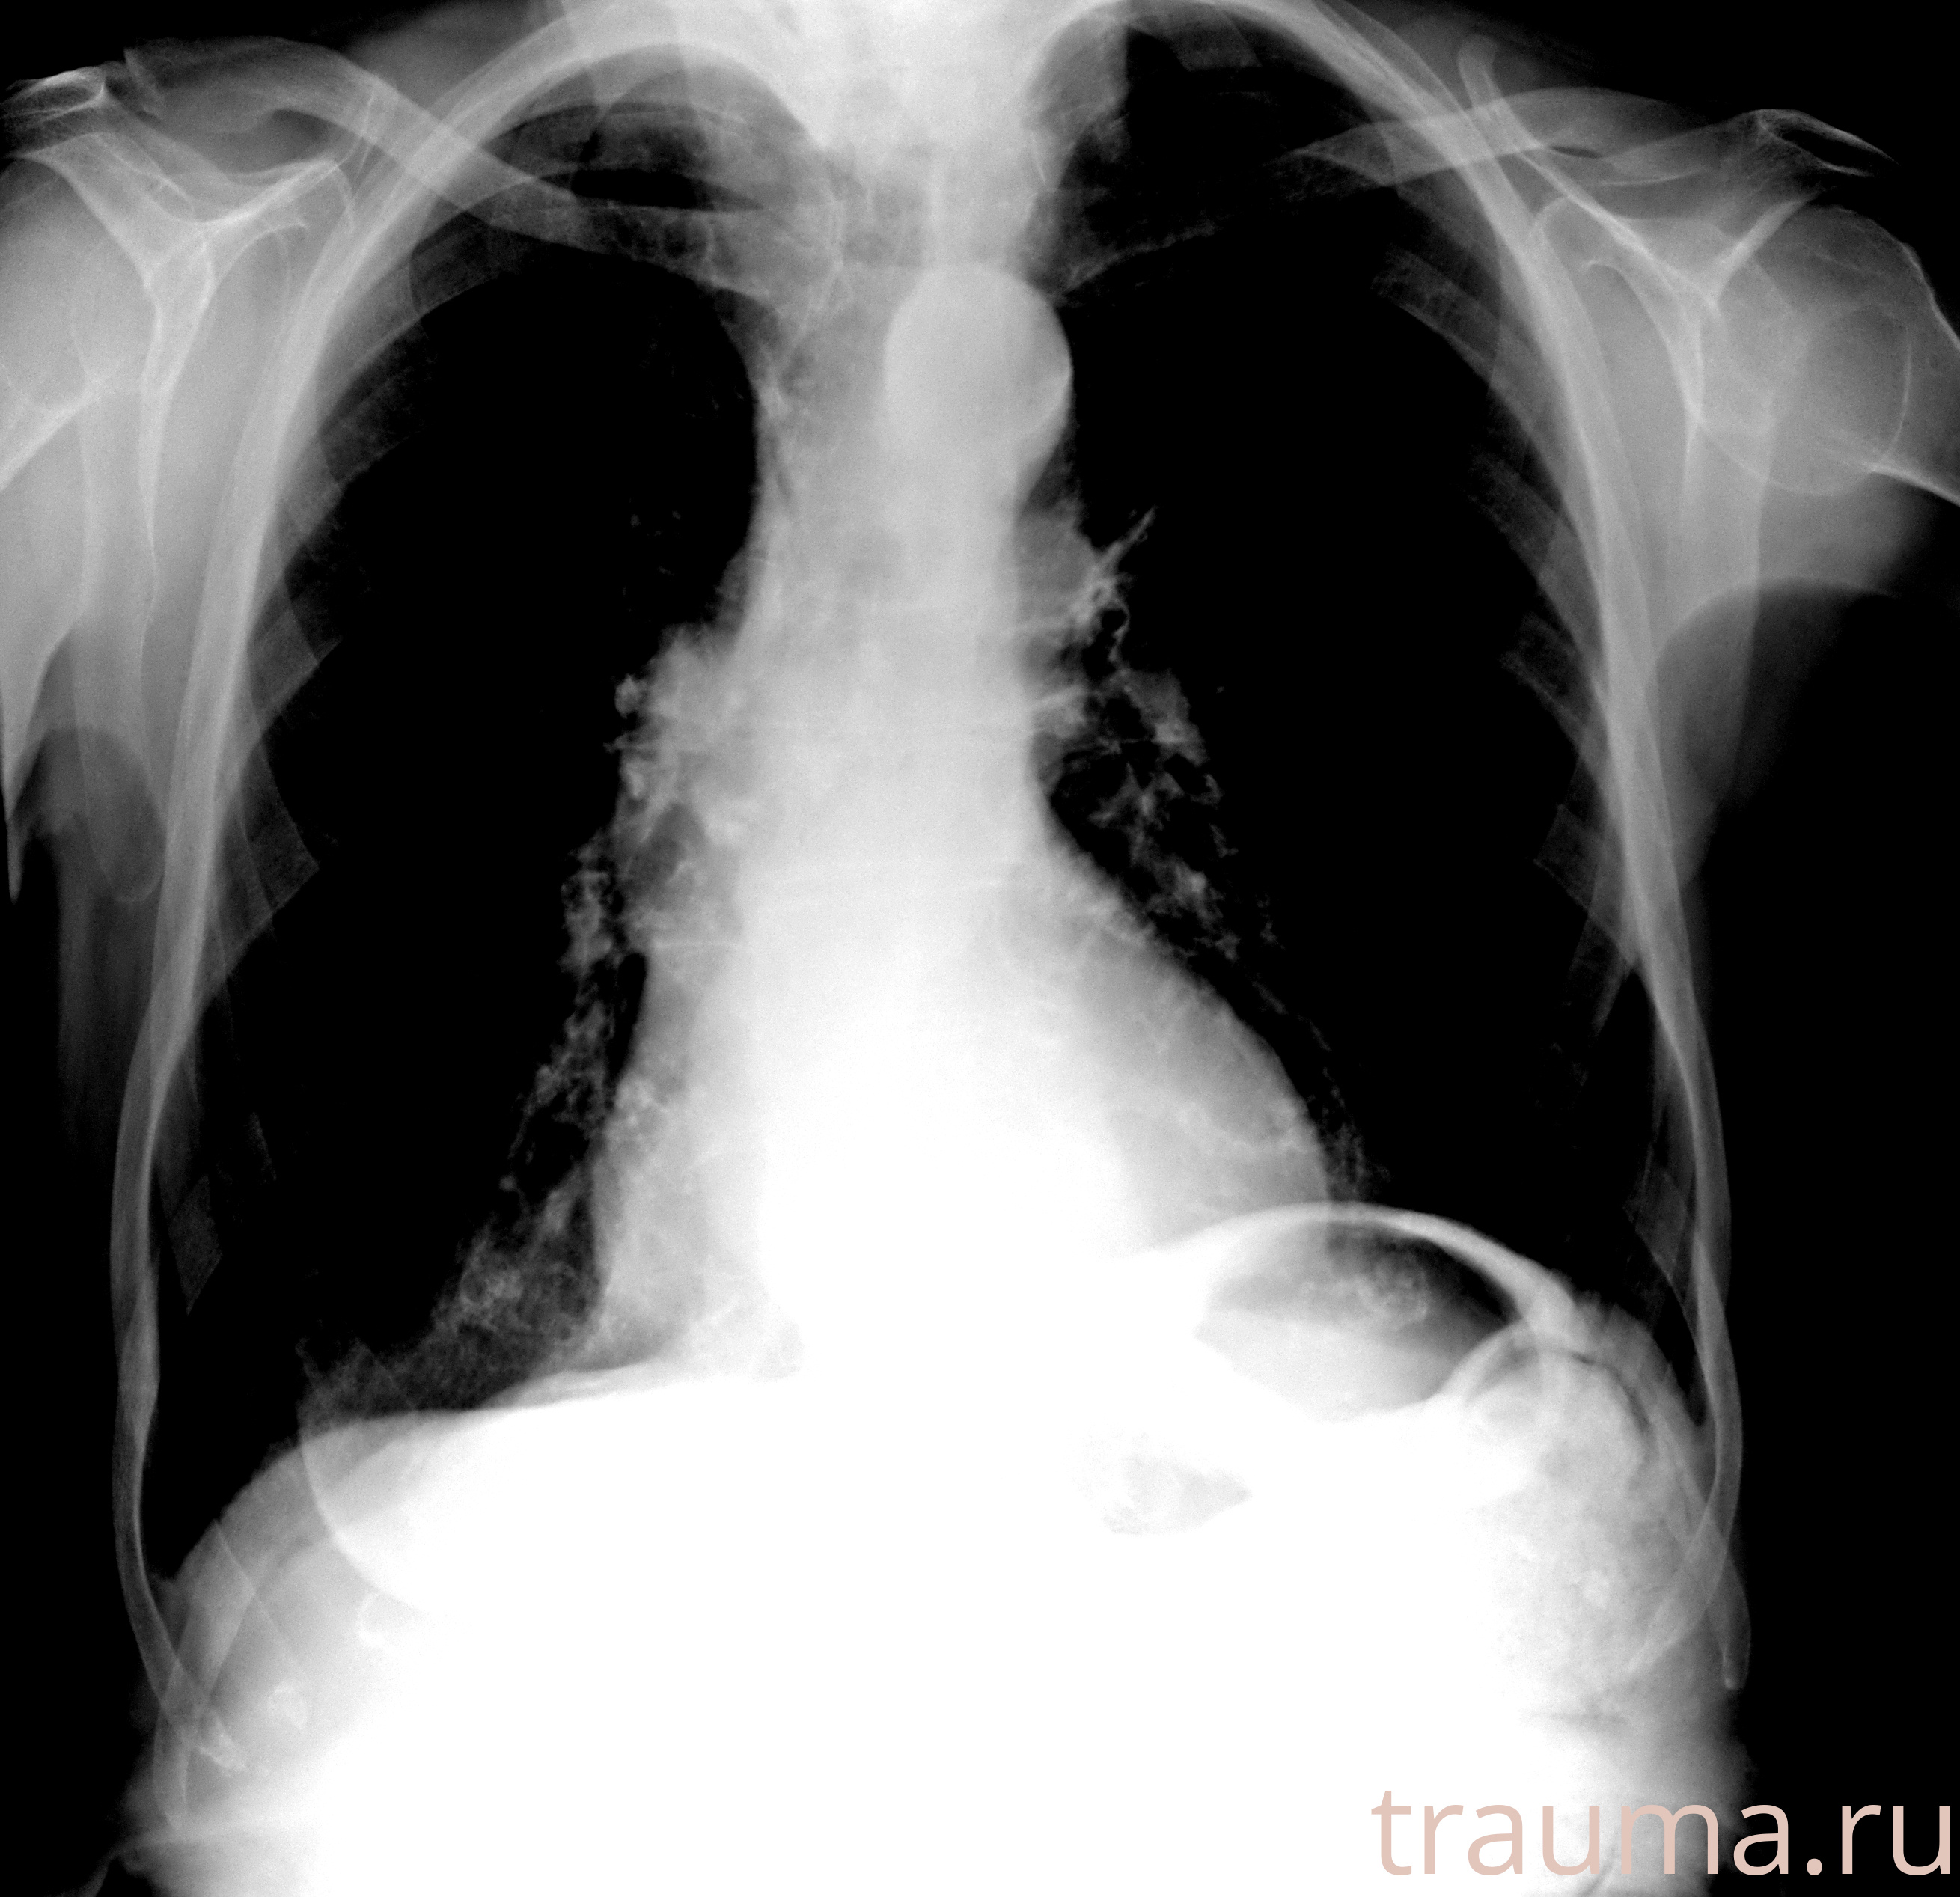

Рентгенограммы

Рентген на дому: по вашему адресу приезжает врач-рентгенолог, травматолог-ортопед с мобильным рентгеновским аппаратом, проводит диагностику травмы или заболевания, делает необходимые рентгенограммы, дает рекомендации по дальнейшему лечению. Получить качественные снимки в домашних условиях возможно благодаря уникальной методике, разработанной МосРентген Центром для института  Склифосовского

при переломе шейки бедра и пневмонии от компании МосРентген Центр - партнера Института имени Склифосовского